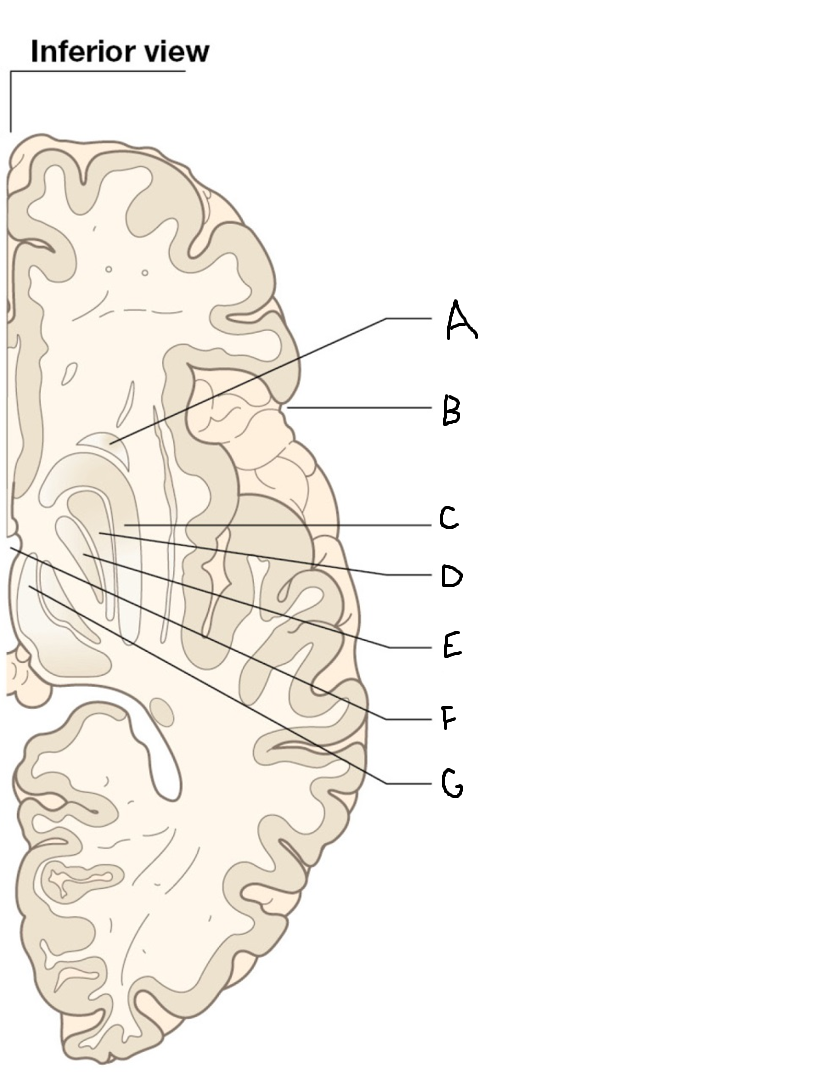

A

internal capsule (anterior limb)

B

caudate nucleus body

C

caudate nucleus head

D

putamen

E

caudate nucleus tail

F

thalamus

G

internal capsule (posterior limb)